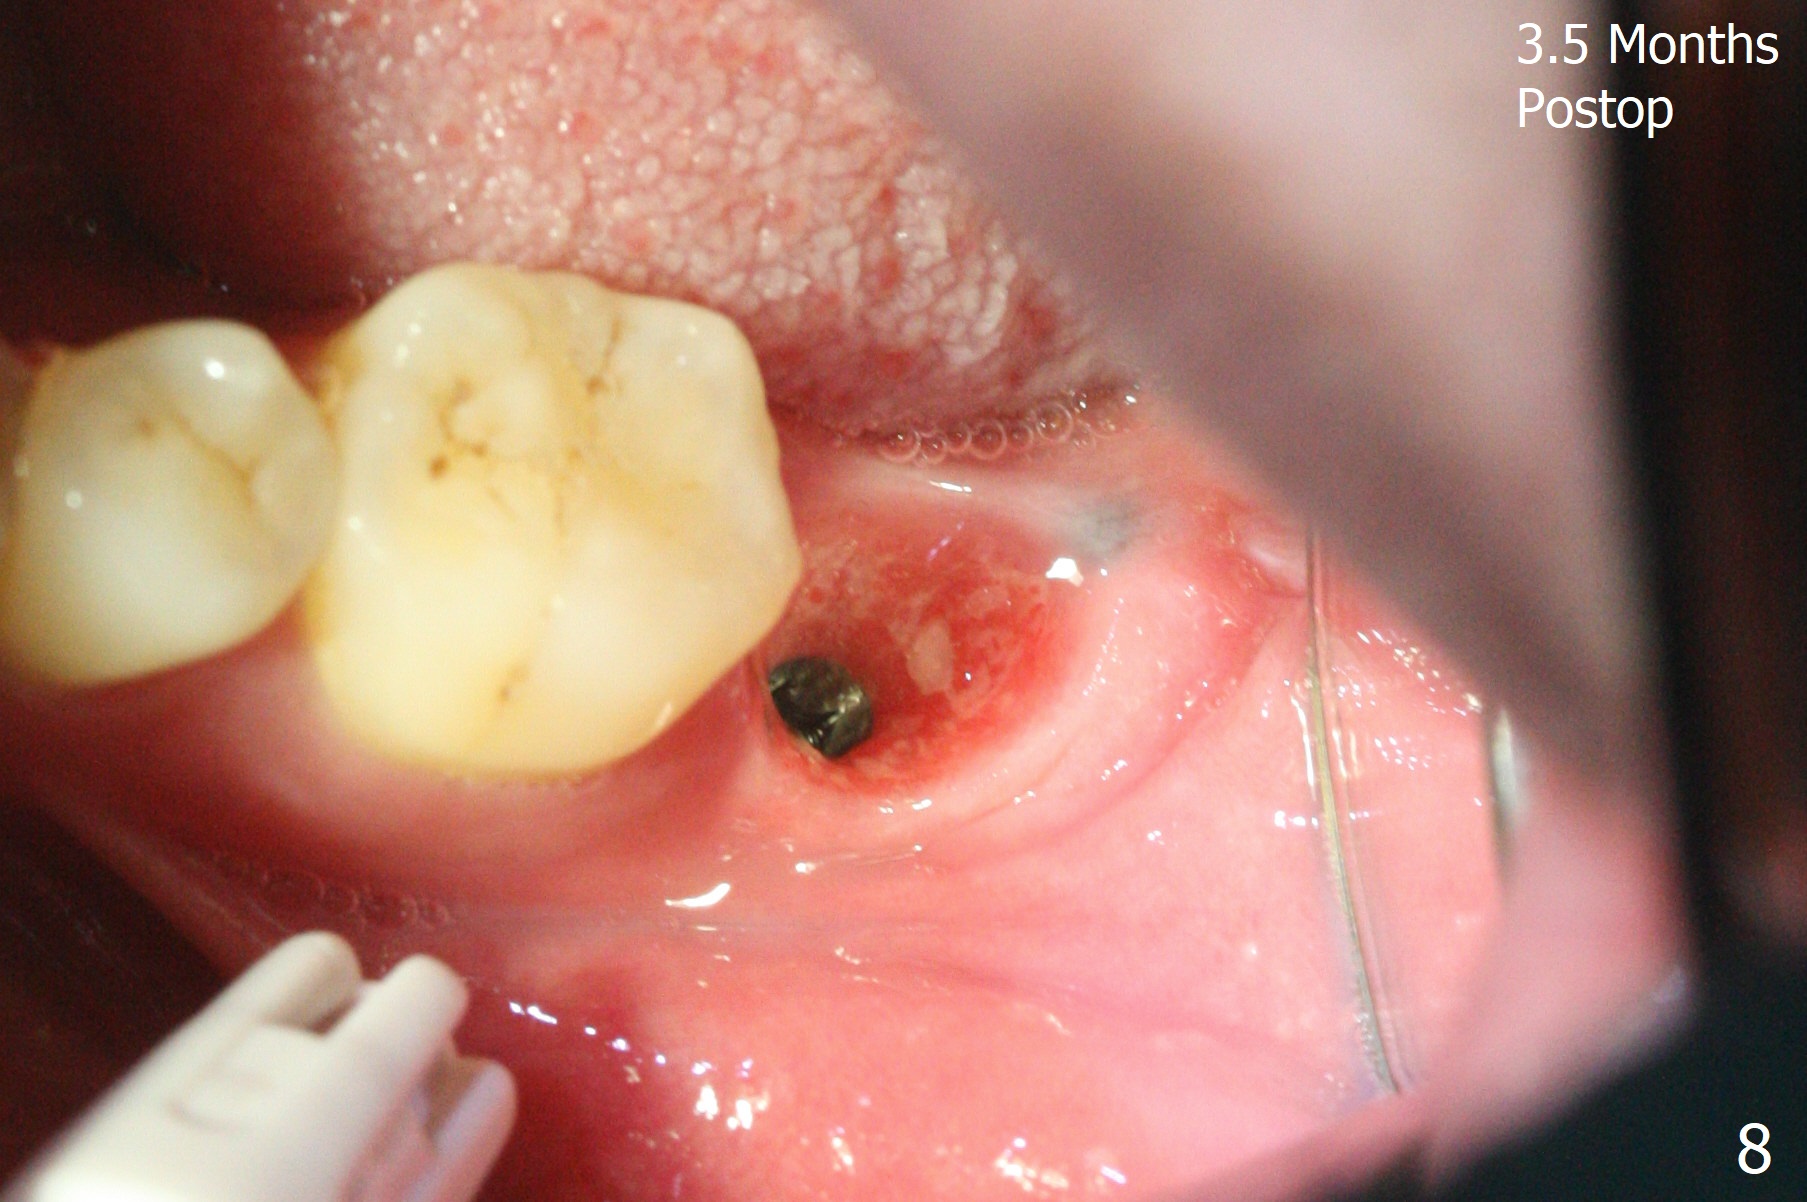

After placement of a 5x11 mm implant and cover screw at #18, allograft mixed with PRF (sticky bone) is placed in the peri-implant space, but it appears that bone density in the apical region (Fig.1 A) is lower than that in the coronal one (C) because of a constriction between the implant and the distal crest (*). Ideally the undercuts (Fig.2 *) of the extraction socket (black area) should be identified. Place bone graft in the undercuts (Fig.3 red circles) after osteotomy (white outlines) and before implant placement! A 4.5x1 mm temporary abutment is placed for an immediate provisional. The 2nd shortcoming of this case is that the implant is placed a little buccal. The papilla mesial to the immediate provisional (Fig.4 P) looks normal 4 days postop (no food impaction is expected when a final restoration is cemented). Additional acrylic (*) was placed to close a buccal gap when the provisional was seated with the temporary abutment. The patient reports loss of a piece of material in 4 days. It must be the additional acrylic, since it is absent 6 weeks postop (Fig.5). The provisional (Fig.5 P) looks wide, probably related to post-extraction gingiva and bone atrophy (Fig.6, 7 *). Bone graft (Fig.6 <) becomes a component of the gingival cuff. The provisional is re-trimmed for better oral hygiene. The gingival cuff is basically healthy 3.5 months postop, although the temporary abutment is loose and the implant is tender to rewinding and winding (Fig.8). The implant seems to remain non-osteointegrated 3.5 months postop (Fig.9). Although the bone density around the implant increases nearly 6 months postop (Fig.10), the implant remains tender when a 5x4(4) mm pair abutment is tightened. The healing abutment is reused. The bone density around the implant increases 11 months postop (Fig.11). Uncover is done with 5.5 mm profile drill. One month post uncover (12 months postop), the implant remains unstable (Fig.12). Prepare sticky bone x1. Make incision for exploration, including retightening the implant after Titanium brush and H2O2 Q-tip rubbing. If needed, a larger and shorter UF implant is a replacement (Fig.13). The implant is removed, cleaned with Titanium brushes and H2O2 in vitro and repositioned 12 months postop (Fig.14: arrow (gaps: post granulation tissue removal)). The gaps are regrafted with sticky bone and covered with PRF membrane and Cytoplast. Although the patient complains of severe pain the first 2-3 postop, the wound is apparently healing 12 days postop. The Cytoplast is exposed asymptomatic 5 weeks postop (Fig.16) and removed (Fig.17). The wound appears to have healed without loss of the bone graft (Fig.18).术后四个月伤口愈合,骨粉几乎没有丢失,有骨小梁形态(图十九:*)。切开,刮匙去骨,有一定硬度,即刻放置修复基台,完全就位(图二十),制备临时牙冠,牙周敷料固定组织瓣(没有缝线)。